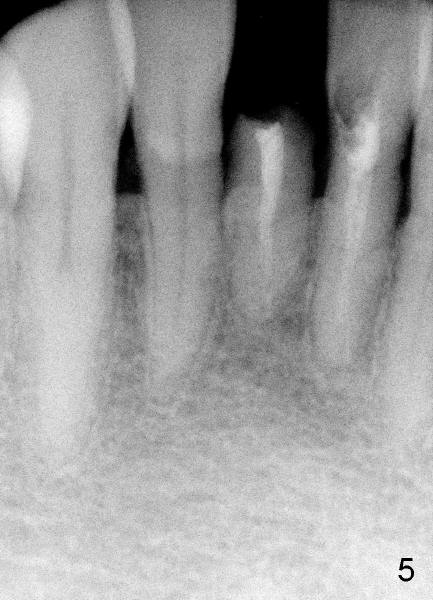

Dear Dr. Borgner: Thanks for the advice again. The patient showed up this afternoon. The tooth (in fact #25 in Fig.5) is pretty badly broken down, but the patient is not ready for implant right now. Prefabricated post and temporary crown are provided. Fig.6 shows the longest post space that can be gained. The mesiodistal dimension of the tooth is 3 mm above gingiva clinically; the buccolingual 5 mm; the minimal dimension between #24 and 26 is 3.5 mm. There is plenty of height. The longest one piece tapered implant from Tatum Surgical is 17 mm. The appropriate implant should be 3x17 or 3.5 x17 if the proximal surfaces of #24,26 are to be trimmed further. This was done when the temporary crown was fabricated. Anyway, thanks for guidance.